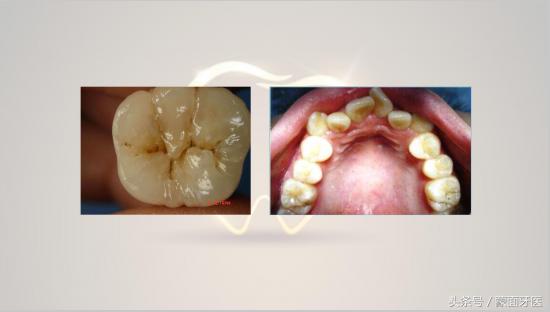

补牙前后